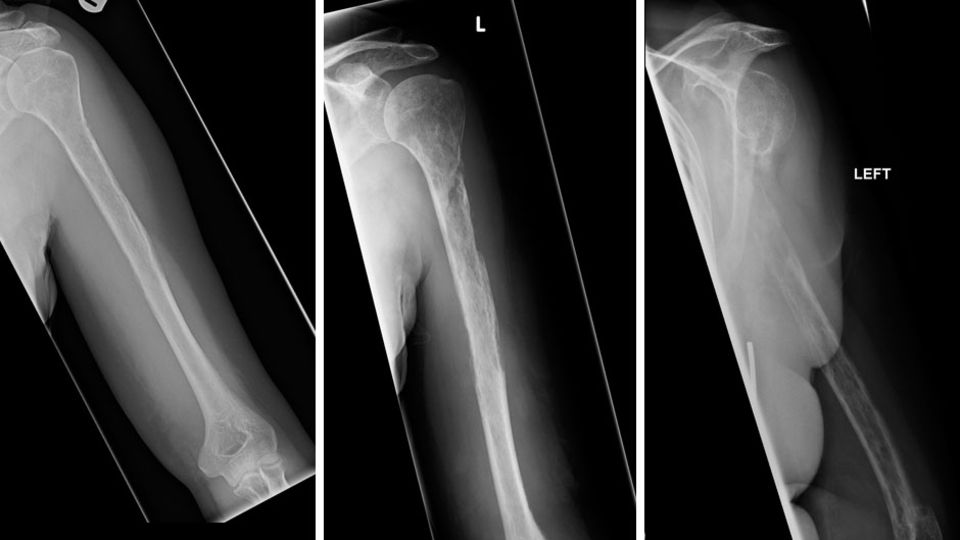

Zwölf Monate nach dem ersten Arzttermin kommt die Frau wieder in die Praxis: Ihr Arm schmerzt weiterhin, außerdem ist er nun zusätzlich geschwollen. Als die Ärzte eine zweite Röntgenaufnahme anfertigen, sind sie verblüfft: Der Knochen ist im Begriff, sich aufzulösen und erscheint porös. Eine weitere Gewebeentnahme zeigt, dass Blut- und Lymphgefäße in den Knochen wuchern. Körpereigene Zellen - sogenannte Osteoklasten - scheinen das Knochengewebe zu attackieren und zu zersetzen. Die umliegenden Knochen erscheinen jedoch intakt.

Einen Monat später ergibt eine erneute Röntgenaufnahme, dass nun auch der Unterarm von dem Zerfall betroffen ist. Die Ärzte stellen daraufhin die richtige Diagnose: Die Frau leidet an der Gorham-Stout-Erkrankung (GSD). Das Krankheitsbild wurde erstmals 1954 beschrieben. Etwa 200 Fälle des seltenen Knochenabbaus sind seitdem bekannt geworden.